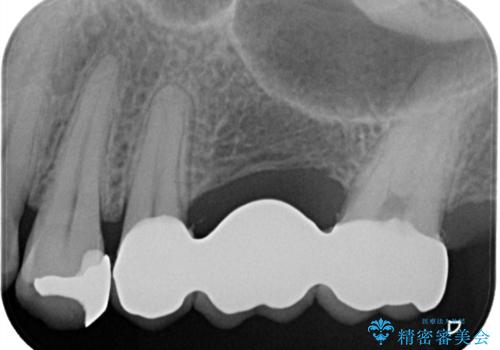

左上7番遠心マージン不適を認め、そこに汚れが停滞していたためやり替えをおすすめし、汚れが付着しずらく審美性に優れたセラミッククラウンブリッジでのやり替えとなりました。

保険適用のメタルインレーを除去したところ、ポンティック部の過度な加圧によって歯肉が強く発赤していたため、一度仮歯に置き換え歯肉の治りを待った後、適切な加圧強さのオールセラミッククラウンブリッジをセットしています。